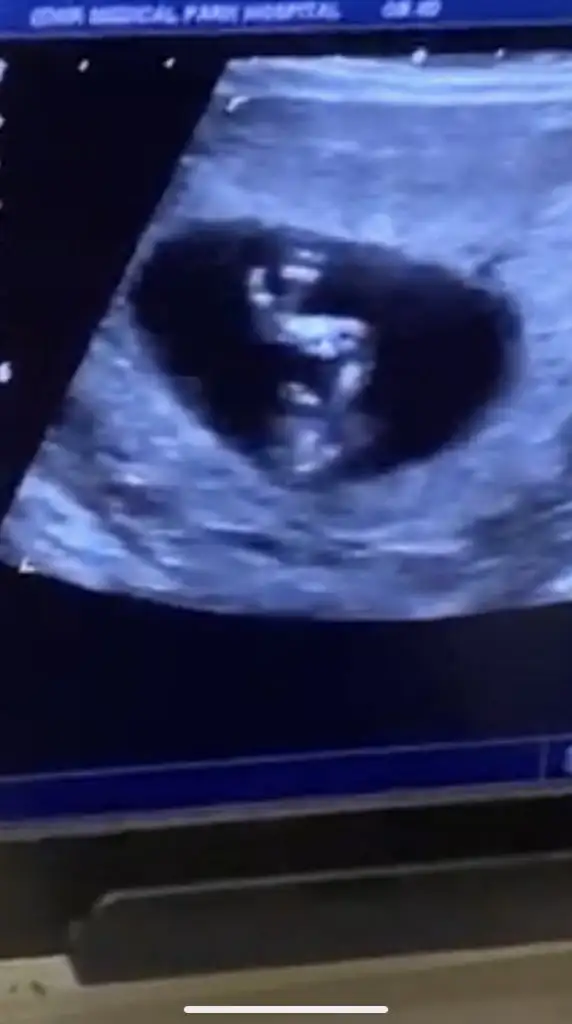

MaşAllah canım 33haftalıksın sanırım demi benle aynı hafta maşallah gelişimi çok güzel bebeğinin Rabbim hayırla kucağına almayı nasip etsin acaba neden almadı nstye sordunuzmuCanlar kontrolden geliyorum bebegimin durumu gayet iyi 2500 kg olmus 1 hafta önden gidiyor, dr bir sıkıntı görmedi ama nst ye bağlamadı